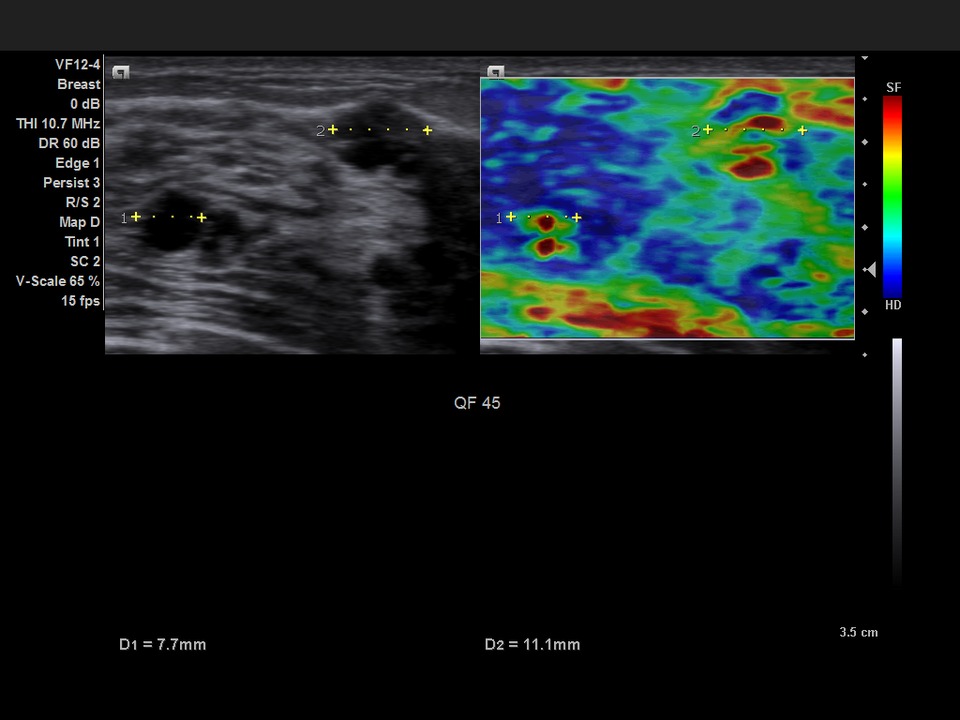

Компрессионная эластография. Предоставляет информацию о жесткости тканей, что важно при дифференциальной диагностике доброкачественных и злокачественных новообразований в молочной железе, щитовидной железе, предстательной железе и других органах. Эластография дополняет В-режим и повышает диагностическую достоверность, особенно в онкологических исследованиях.

- eSie Touch™ Elasticity Imaging — визуализация параметров эластичности с использованием компрессионной эластографии.